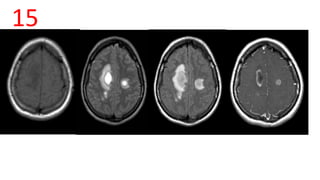

15

ADEM

• T2 and FLAIR: high signal, with surrounding oedema -situated in subcortical

locations; the thalami and brainstem can also be involved

• T1 C+ (Gd): open ring sign

• DWI: there can be peripherally restricted diffusion

ADEM • T2 andFLAIR: high signal, with surrounding oedema -situated in subcortical locations; the thalami and brainstem can also be involved • T1 C+ (Gd): open ring sign • DWI: there can be peripherally restricted diffusion